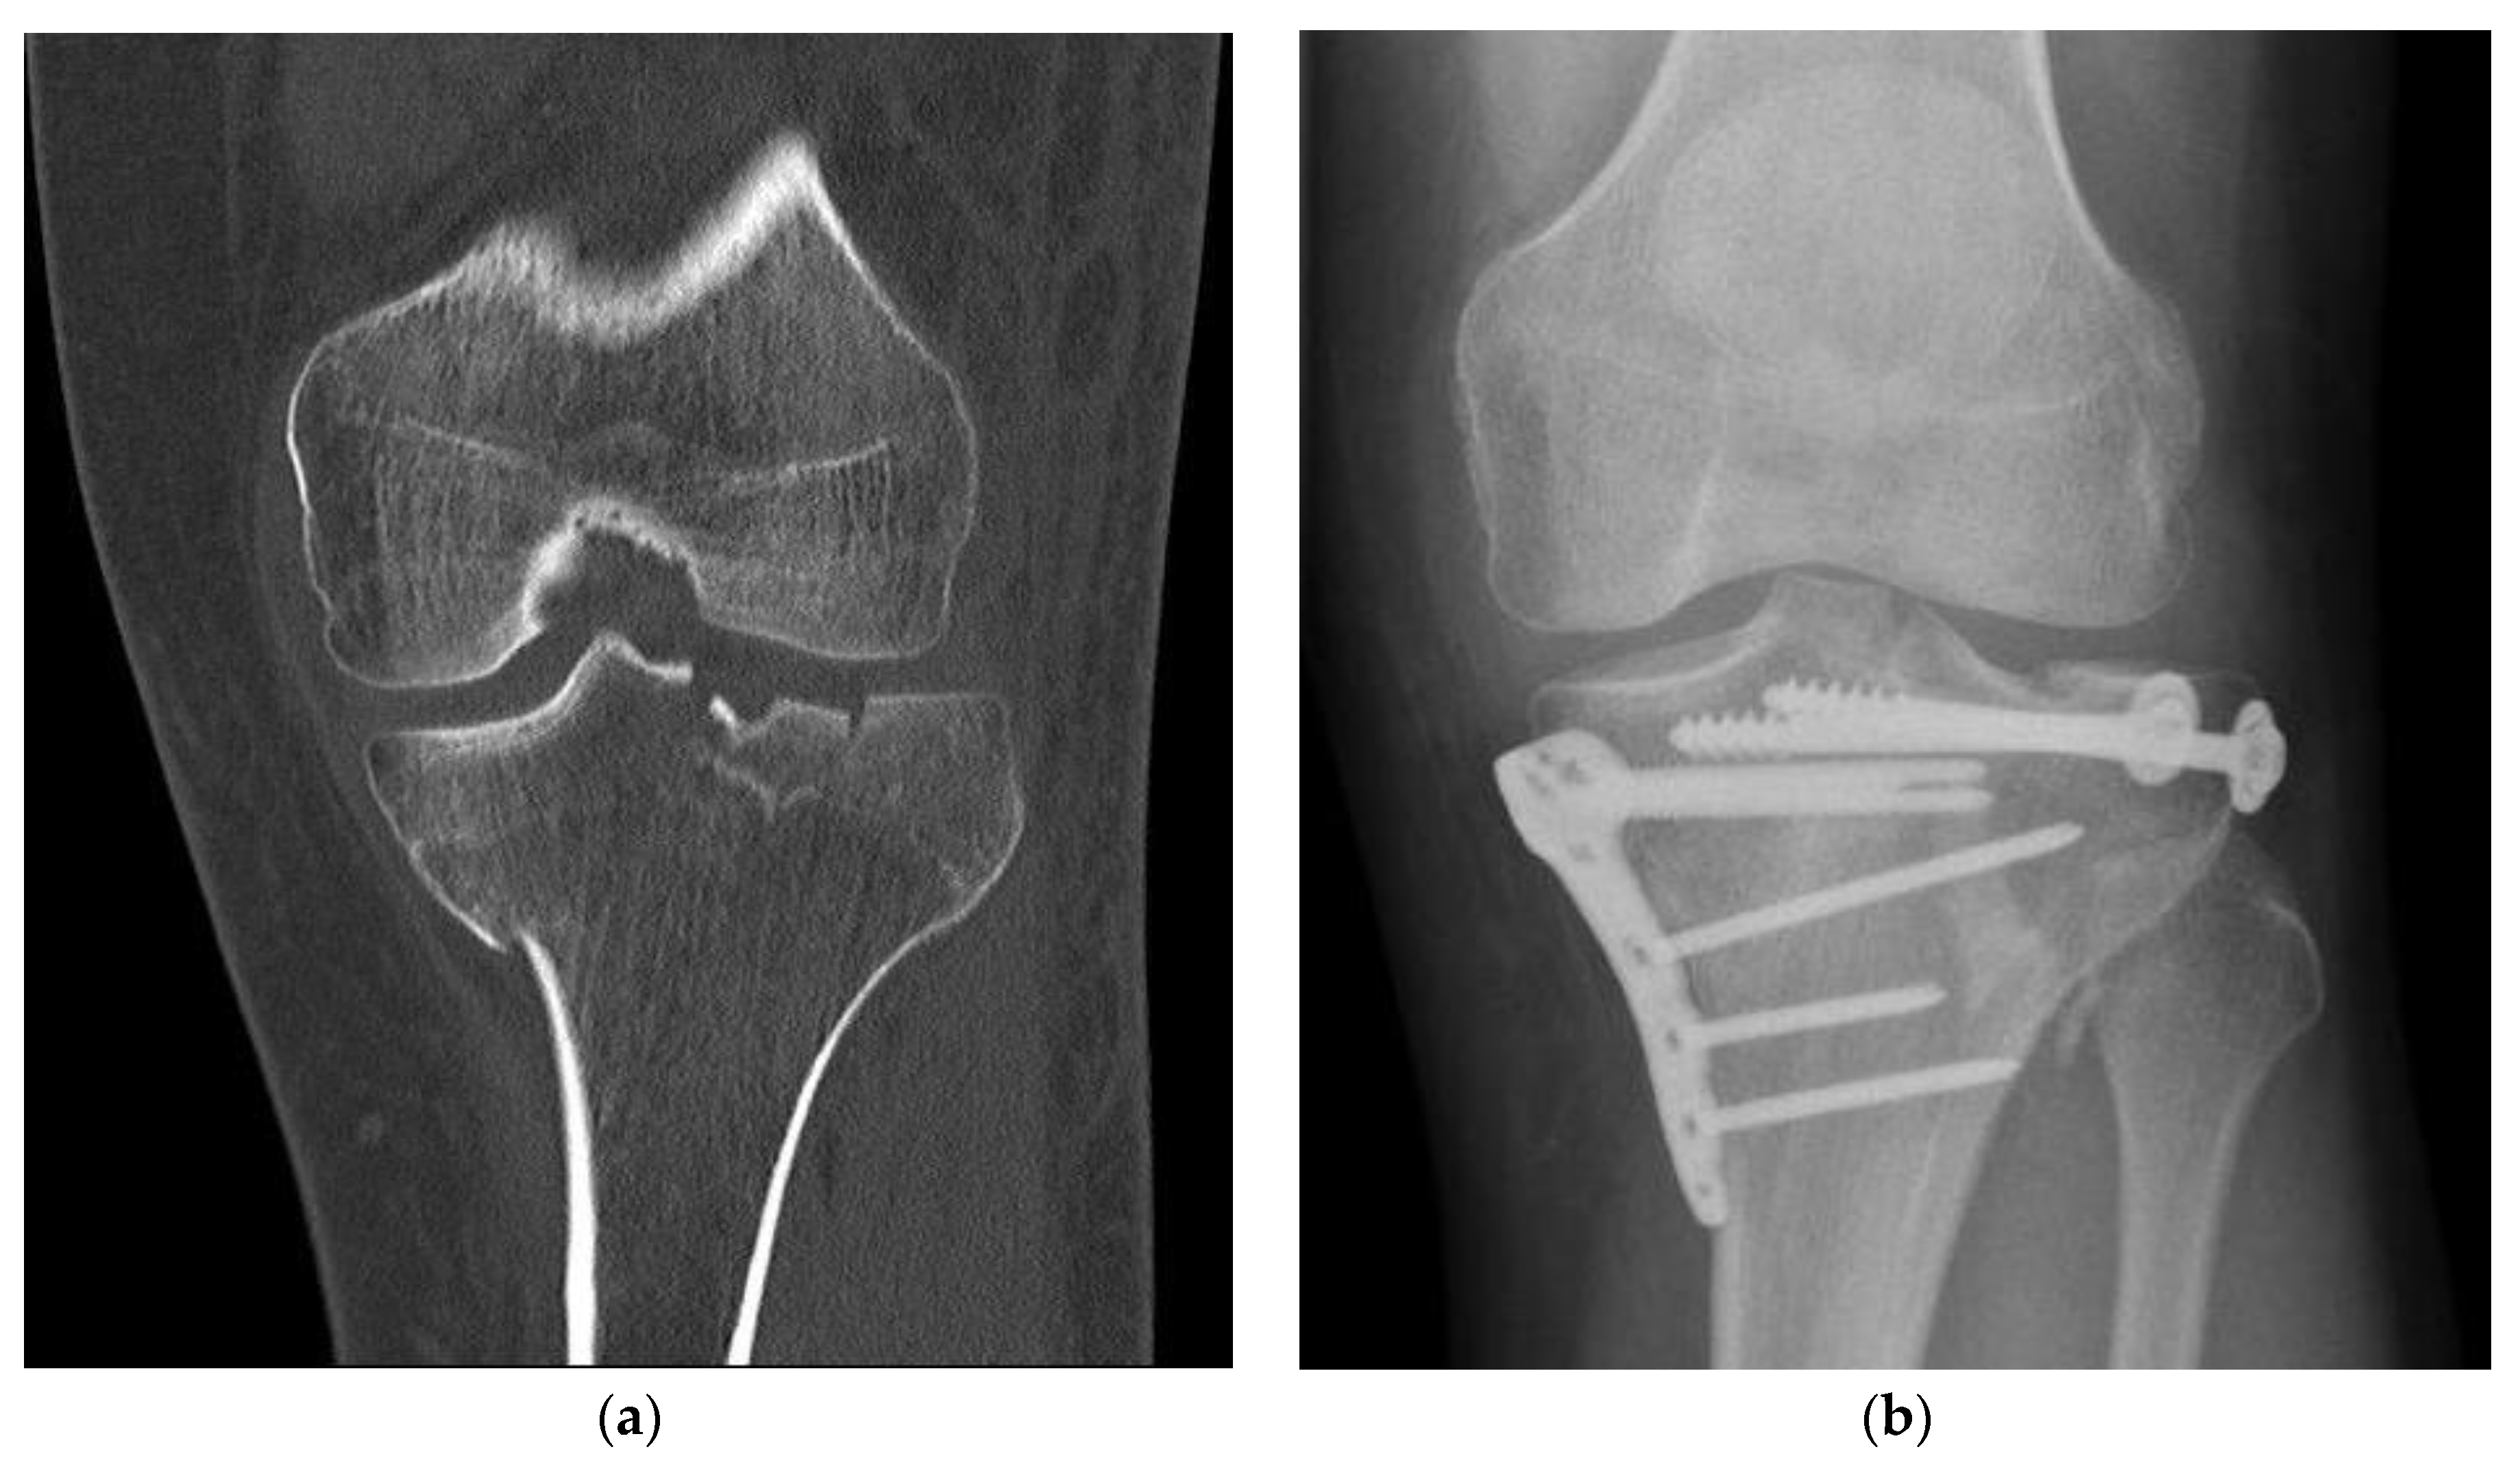

Treatment, complications, and healing progression were radiologically examined (Figure 2). This is important to assess the performance and safety of the BSM as registered medical devices which are products with a medical purpose that are intended for use in humans. Although CT imaging can provide better and more detailed analysis, however, due to radiation laws in Germany, CTs are only performed when X-rays are not informative enough. Furthermore, the retrospective study limits the choice of methodology. In this study, each patient record was evaluated with up to 6 follow-up examinations (FU). To achieve a non-biased assessment, the radiographic double-blinded examination was done by 2 independent evaluators. To determine bone healing, a classification system was developed based on the previously reported criteria set by Bohnhof et al., Freyschmidt et al. and Islam et al. to achieve an enhanced evaluation of the fracture edges, fracture gaps, and articular surface [15,16,17]. Regarding the fracture margin, sharp edges (5), partially sharp and partially blurred edges (4), blurred edges (3), faintly visible edges (2), and no visible edges (1) were distinguished. The bridging process indicates the new bone tissue grows to fill the fracture gap and is assessed by its mineralization and localization in the gap. A visible edge was seen in fractures without consolidation (6).

Figure 2. Fracture treatment of a proximal tibial fracture by surgical bone substitute material augmentation: (a) Preoperative CT scan demonstrates a metaphyseal compression fracture with intra- and extraarticular fracture gaps; (b) Alloplastic bone material substitute augmentation replaces the bone material of the fracture vault defects.